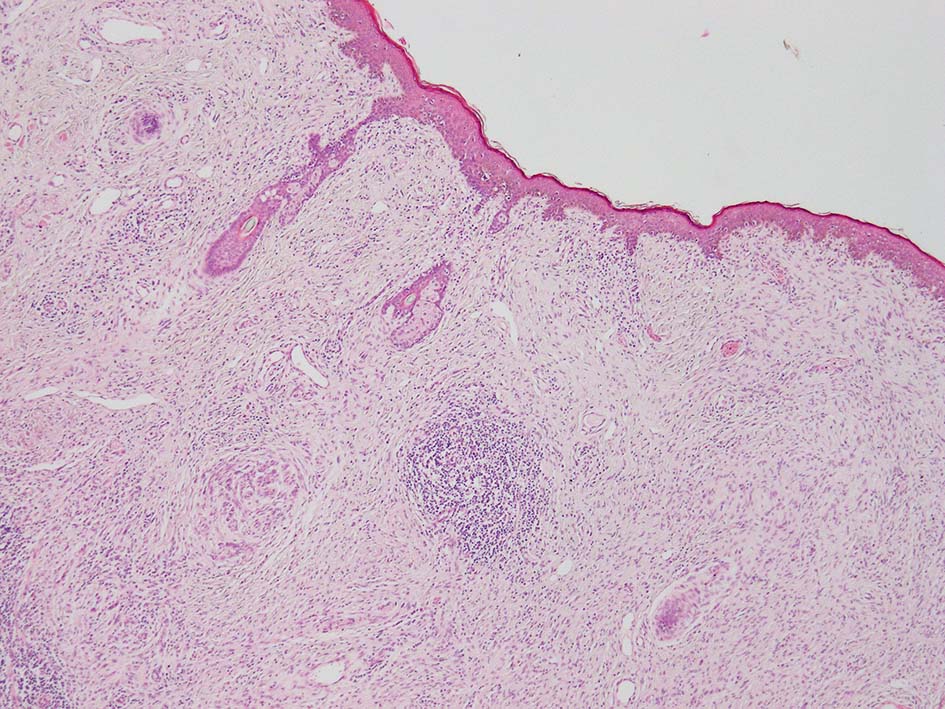

初回皮膚生検組織

リンパ濾胞が細血管周囲に形成され, この部分に異型といえる細胞が増加している(S100+)